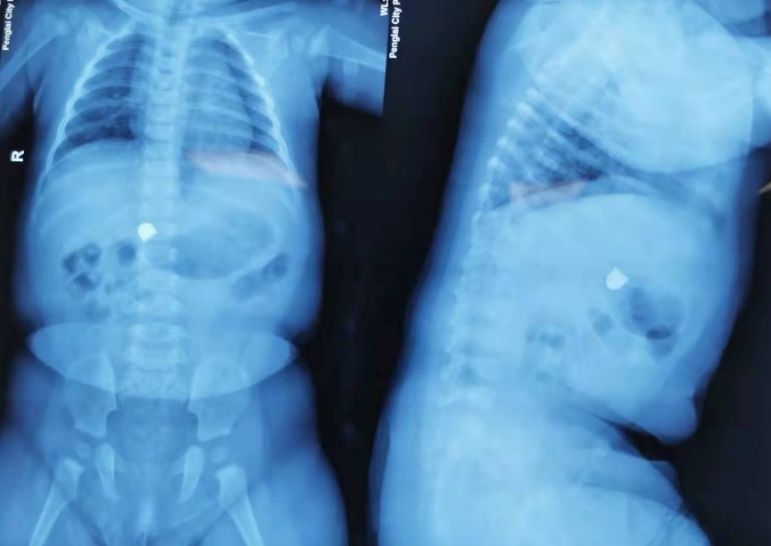

10月7日深夜0点,一位6个多月的小女孩误吞金属异物2小时后被紧急送到了我院。考虑到金属异物的一端带有锐利棱角,儿科消化内镜医护人员迅速集结,在最短的时间内为患儿完成急诊胃镜手术,化险为夷。